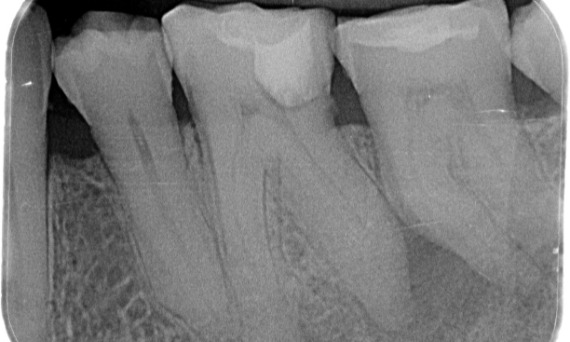

До: При осмотре обнаружено кариесное поражение правого нижнего первого моляра. Рентгенологическое исследование выявило близость поражения к рогу пульпы и в сочетании с основной жалобой был поставлен окончательный диагноз: хронический необратимый пульпит.

После: Доступ к полости выполнялся максимально консервативно. TruNatomy была системой выбора из-за молодого возраста пациента. Нам необходимо было максимально сохранить дентин, чтобы повысить способность зуба преодолевать окклюзионную нагрузку и увеличить долговечность окончательной реставрации.